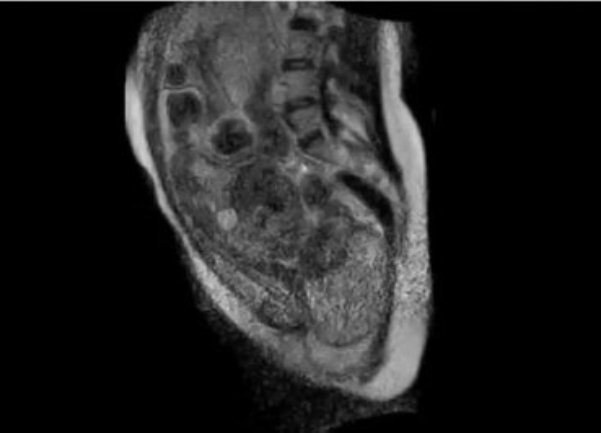

Ljekari berlinske bolnice Šarite napravili su snimak porođaja "iznutra", uz pomoć specijalnog, otvorenog skenera za magnetnu rezonancu i time ušli u istoriju, jer je ovo prvi put da nastaje takav snimak. POGLEDAJTE FASCINANTNI VIDEO!

porodjaj iznutraSnimak traje 30 sekundi i prikazuje tzv. drugu fazu porođaja, tokom koje se majka trudi da izgura bebu korz porođajni kanal, prenosi Blic.rs.

Prema riječima ginekologa Ernsta Bernda, porođaj je protekao normalno, a aparat je snimio sve pokrete i procese koji se odigravaju u materici i porođajnom kanalu, pa je čak ljekarima omogućio i da prate bebine otkucaje srca.

Snimak je obezbjedio dragocene podatke o procesu porođaja, i omogućio je naučnicima da vide detalje kakvi su ranije mogli da se proučavaju samo u simulacijama. Takođe bi mogao pomoći i da se objasni zbog čega oko 15 posto žena mora da se porodi carskim rezom, jer se njihove bebe u porođajnom kanalu ne kreću dovoljno.